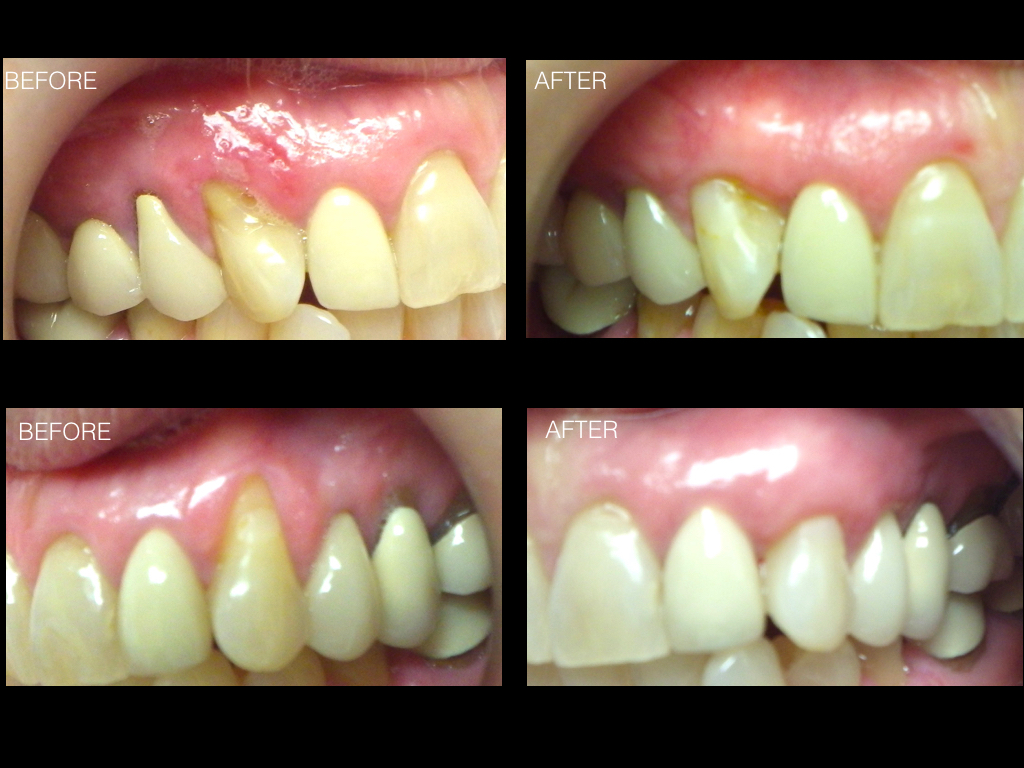

Connective Tissue Gingival Grafting for Gingival Recession